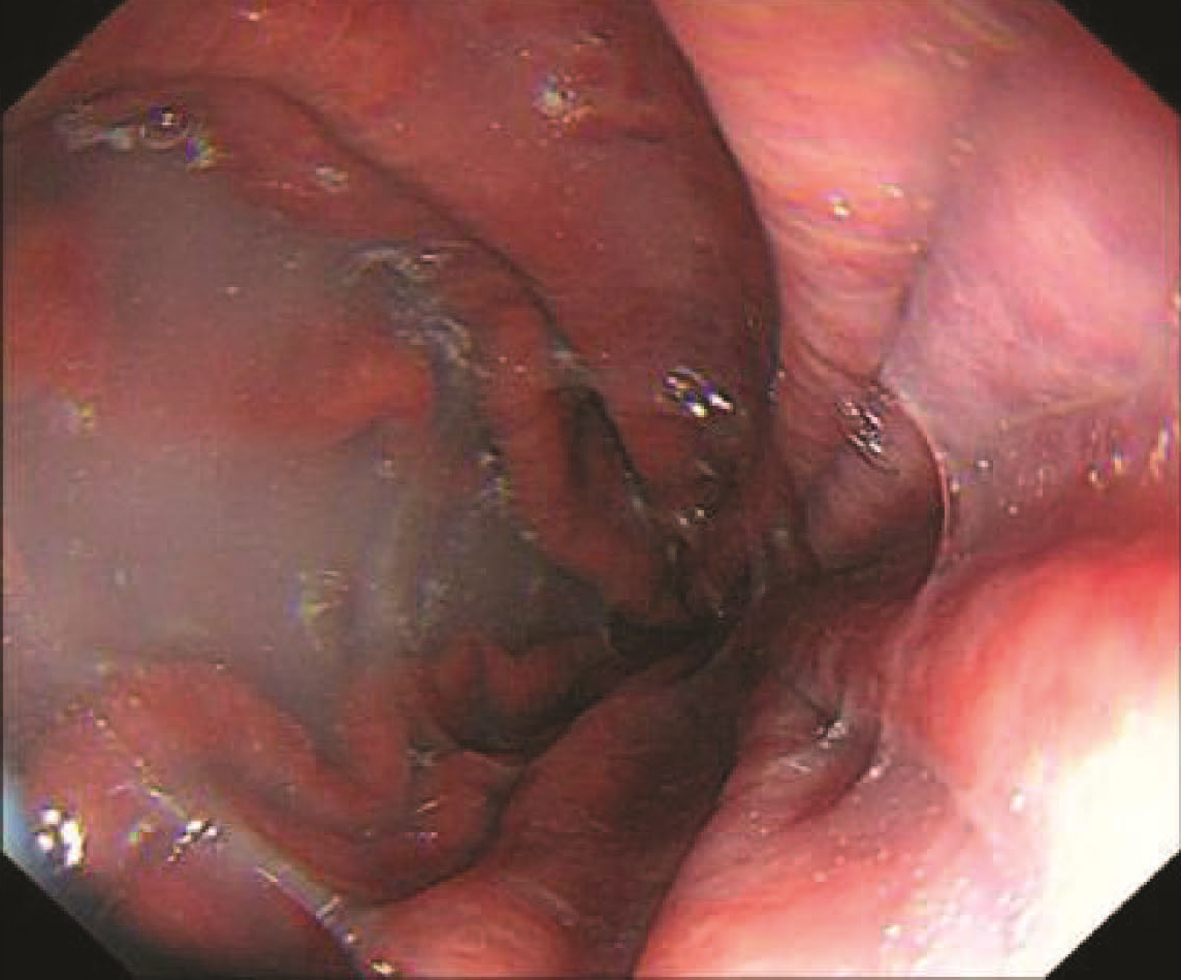

内镜下序贯套扎治疗食管胃伴十二指肠静脉曲张1例报告

文皓, 何朝晖, 蒋彤, 石国庆

2023, 39(3): 637-639. DOI: 10.3969/j.issn.1001-5256.2023.03.024

摘要(891) HTML (275) PDF (2676KB)(111)

摘要: